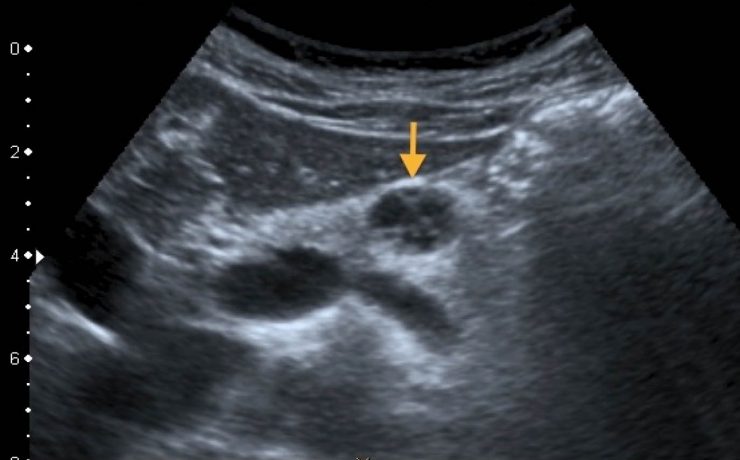

El presente artículo tuvo el objetivo principal analizar la funcion sexual en mujeres portadoras de miomas durante un año, tomando en cuenta el no deseo sexual, la falta de excitación, la falta de orgasmo, presencia de dispareunia y dolor pélvico. El mioma es el tumor solido más frecuente en la